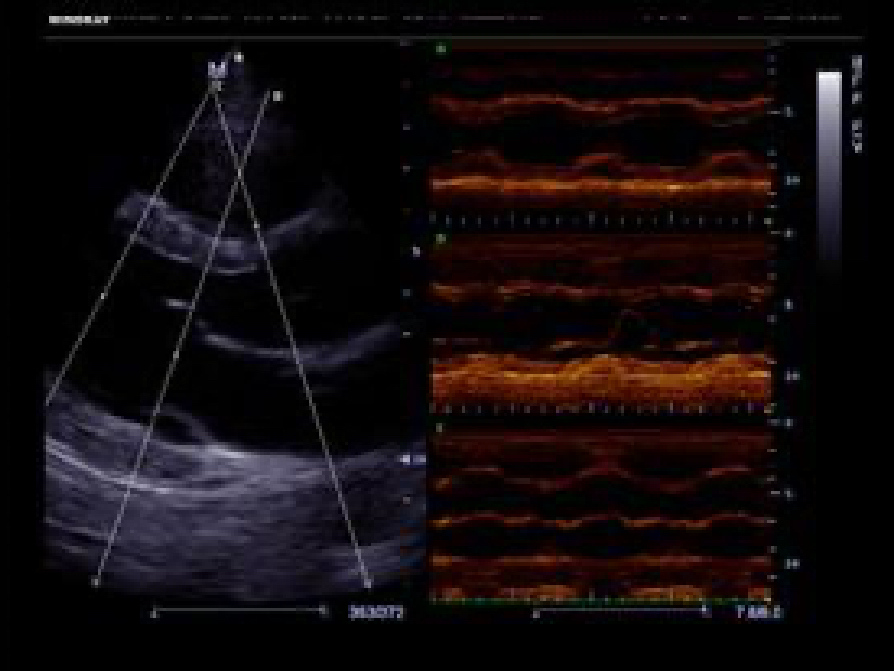

A fully-featured laptop style color Doppler system, M5 offers uncompromised 2D performance and exceptional value in a highly convenient and easy to use package. The portable, simplistic nature of the M5 makes it ideal for a variety of hospital and office environments.

PSHITM (Phase Shift Harmonic Imaging)

Purified Harmonic Imaging for better contrast resolution providing clearer images with excellent resolution and less noise.

Permits use of multiple scanned angles to form a single image, resulting in enhanced contrast resolution and improved visualization.

iClearTM (Speckle Suppression Imaging)